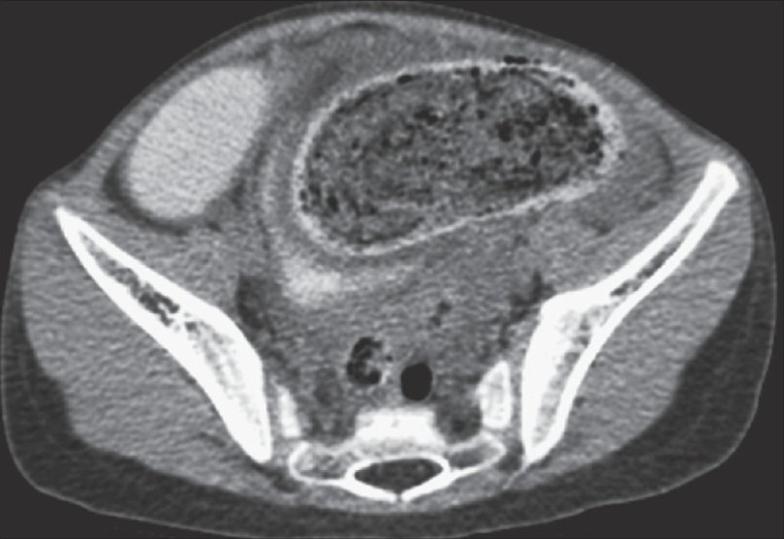

伴有穿孔的末端回肠毛粪石:一种罕见表现并文献复习

Terminal ileal trichophytobezoar with perforation: A rare presentation with review.

Trichophytobezoars are uncommon foreign bodies, formed by hairs and vegetable matter with impacted food particles. We report an unusual case of a 5-year-old girl with large terminal ileal trichophytobezoar causing perforation peritonitis.

摘要

毛发植物粪石是由毛发、植物物质和嵌塞的食物颗粒形成的罕见异物。我们报告了一例不寻常的病例,一名5岁女孩患有巨大的回肠末端毛发植物粪石,导致穿孔性腹膜炎。